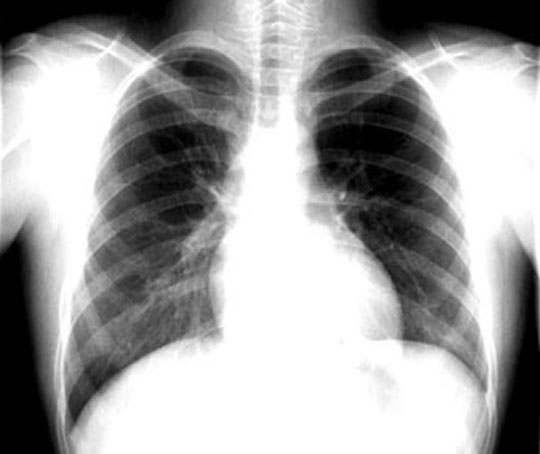

CXR